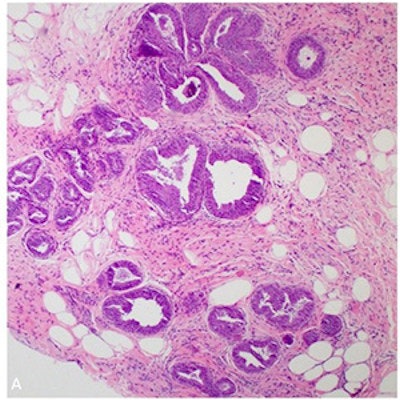

Low-power magnification view of FEA. All images courtesy of the RSNA.

Low-power magnification view of FEA. All images courtesy of the RSNA. High-power magnification view of characteristic FEA features: (straight arrow) Relatively oval and monotonous nuclei, (hooked arrow) prominent apical snouts, (star) luminal calcifications.

High-power magnification view of characteristic FEA features: (straight arrow) Relatively oval and monotonous nuclei, (hooked arrow) prominent apical snouts, (star) luminal calcifications.Treatment of pure FEA can be controversial because published rates of FEA converting to cancer can vary widely. The authors conducted the review to help clarify the best treatment options.